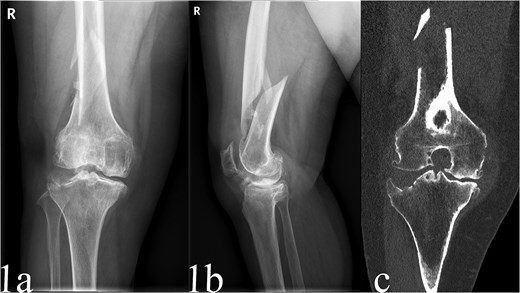

A 68-year-old female with a history of advanced tricompartmental osteoarthritis presented with persistent knee pain and functional impairment following a fall at home. Her OA had been managed conservatively with analgesics and intra-articular injections, but her pain had progressively worsened, impacting her well-being and activities of daily living. Imaging revealed a displaced spiral fracture of the distal femur (AO/OTA type A1.2) and knee OA (Kellgren-Lawrence grade IV) (Fig. 1a and b). Computed tomography (CT) scans further clarified the fracture pattern and cartilage degeneration (Fig. 1c). Laboratory tests were unremarkable except for mild anemia, and bone density assessments confirmed osteoporosis (T-score of −2.8). After thorough evaluation and discussion with the patient regarding treatment options, a single-stage procedure combining ORIF of the femoral fracture with TKA was chosen.

Preoperative anteroposterior radiographs of the case, sustained a displaced spiral fracture of the distal femur (AO/OTA type A1.2) and knee OA (Kellgren-Lawrence grade IV) (a and b). CT scans knee OA (Kellgren-Lawrence grade IV) (c).